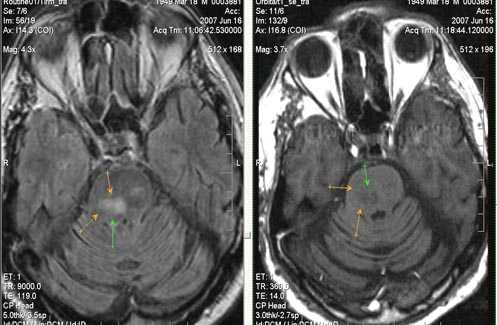

Бассейн кровоснабжения левой верхней мозжечковой артерии, острая стадия НМК.

Ишемическое ОНМК, ствол мозга (подострый период)